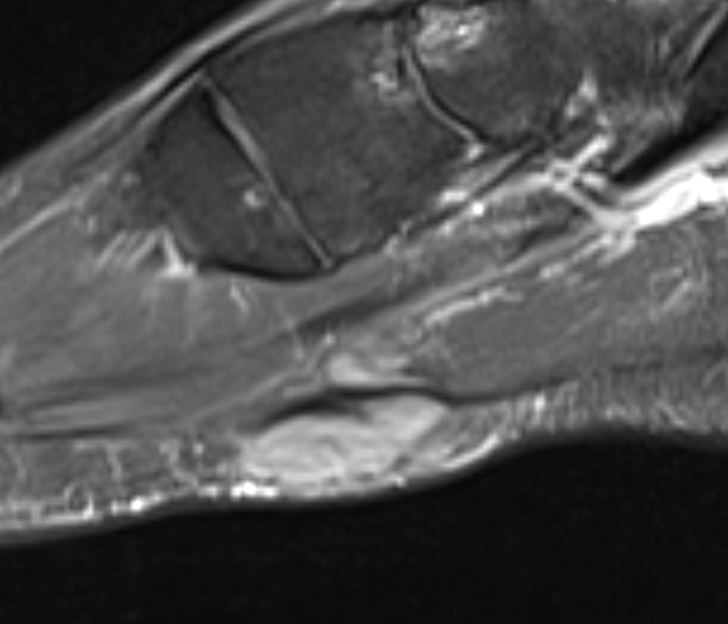

Home Schwerpunkte Krankheitsbilder Morbus Ledderhose Ledderhose MRT sagital PDw

Ledderhose MRT sagital PDw